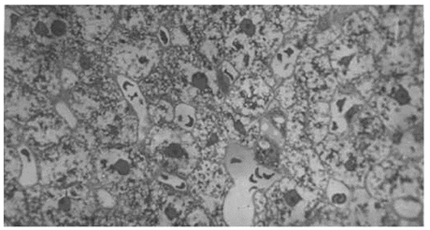

Печень. При гистологическом исследовании цитоархитектоника органа после 5-и часового иммобилизационного стресса на всем протяжении нарушена [4]. Выявляются признаки дискомплексации гепатоцитов с потерей их радиальной ориентации. Местами в гепатоцитах наблюдались дистрофические изменения, вплоть до их распада (рис.3).

Рис.3. Печень, дистрофические изменения в гепатоцитах с очагами некроза. Окраска гематоксилин-эозином, об. 40x10

В сохранившихся печеночных дольках просветы центральных вен, межбалочных синусоидальных капилляров резко расширены и полнокровны. Следует отметить, что на фоне выраженной белковолипидной дистрофии и некроза гепатоцитов выявлялся морфологический субстрат иммунопатологической реакции, проявляющийся периваскулярными лимфоцитарными инфильтратами, напоминающих фолликулы органов иммунной системы. Кроме того, выявлялись также очаги лимфоцитарной инфильтрации вокруг триад долек печени.